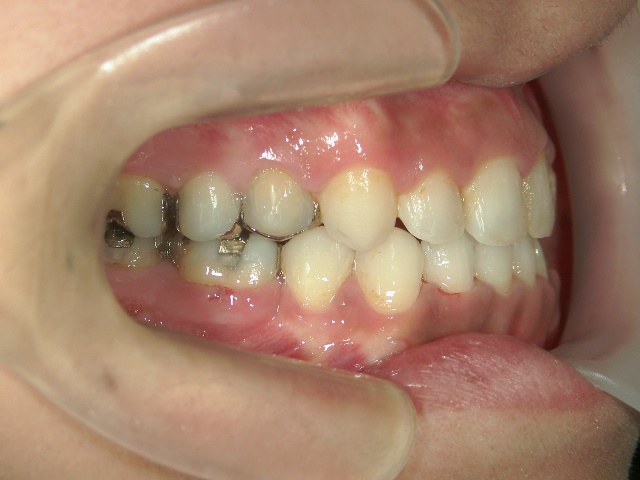

全顎ワイヤー矯正 症例(18)

30歳女性 浜松市北区在住

治療期間3年4ヶ月

主訴:前歯の歯並びが気になる。

矯正歯科 治療前 上顎を装置(QH)で拡大後ワイヤー矯正へ移行、右下5番左下4番 計2本抜歯叢生改善